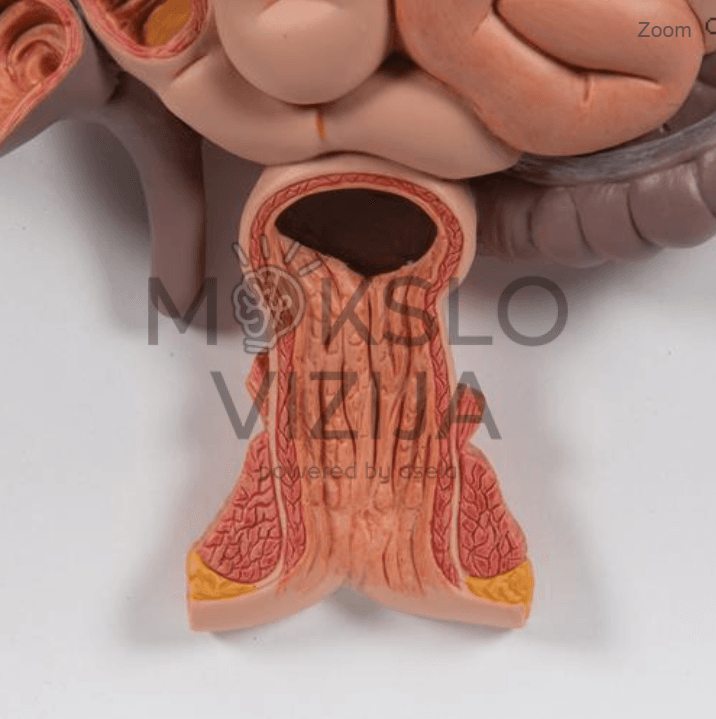

- Tiksli žmogaus virškinimo sistemos anatomija nuo burnos iki tiesiosios žarnos

- Nuimamos dalys: kepenys su skrandžio dalimi, atidaromas skrandis

- Matomi vidaus organų paviršiai ir struktūros